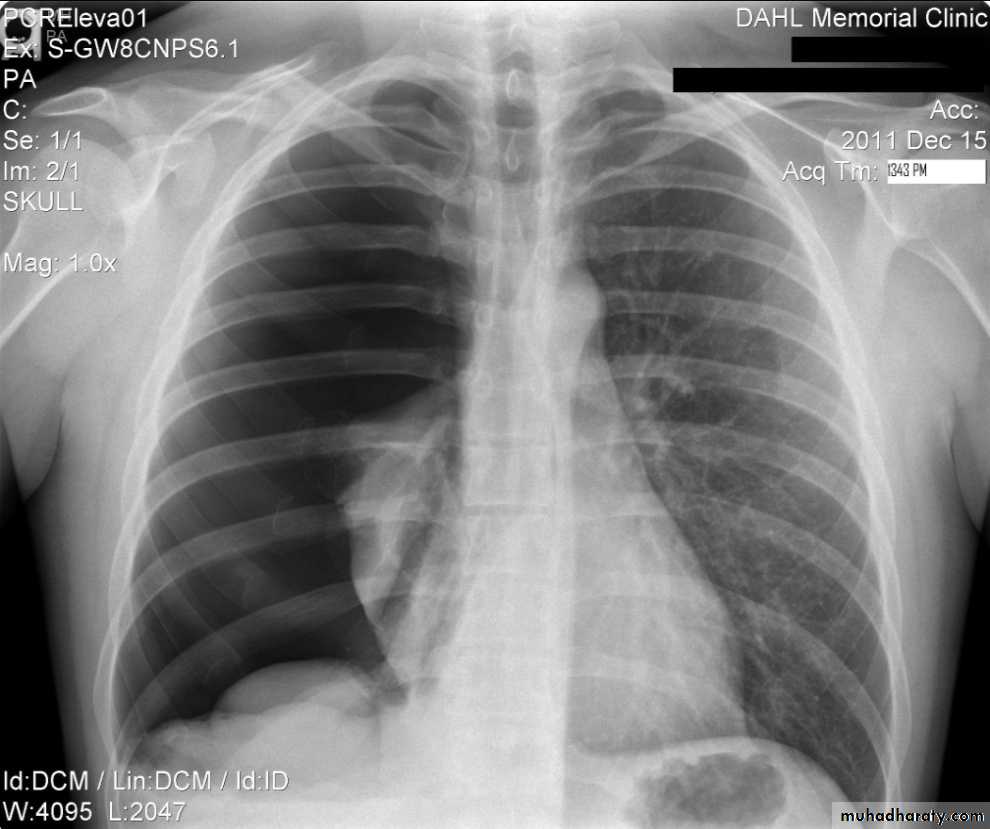

Hydro pnuemothorax

Hydropneumothorax is a term given to the concurrent presence of a pneumothorax as well as a hydrothorax (i.e. air and fluid) in the pleural space.Plain radiographs

On an erect chest radiograph, recognition of hydropneumothorax can be rather easy - and is clasically shown as an air-fluid level. On the supine radiograph, this may be more challenging where a sharp pleural line is bordered by increased opacity lateral to it within the pleural space may sometimes suggest towards the diagnosis 3,

Hydropnemothorax